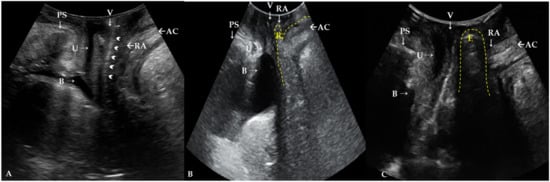

4.2. Role of TLUS in Differentiation of the True POP from Conditions Mimicking POP